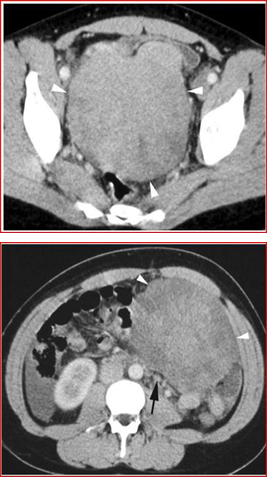

Figures 7 and 8: Axial CT images with contrast medium 7-8 show two masses (arrow points), one in the pelvis (Figure 7) and one in the left iliac fossa (Figure 8). The masses tend to displace the surrounding organs and free fluid is observed in the right area. Small retroperitoneal lymph nodes are also noted in the left paraaortic region (black arrow).

Abdominal and pelvic CT shows two contiguous solid masses. The small cysts on the periphery of the masses, identified by ultrasound and MRI, are not shown by CT which instead highlights the presence of some small retroperitoneal lymph nodes of approximately 1 cm. (Figures 7 and 8). There was no further adenopathy and the spleen was normal. Furthermore, the bone marrow aspirate did not contain infiltrates.